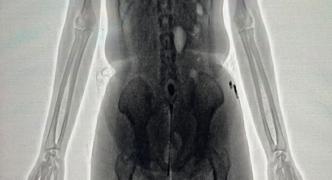

Ao passar pelo equipamento, policiais penais identificaram irregularidades na imagem corporal da visitante, companheira de um interno da unidade. As imagens apontaram a presença de um objeto em formato cilíndrico introduzido na cavidade pélvica.